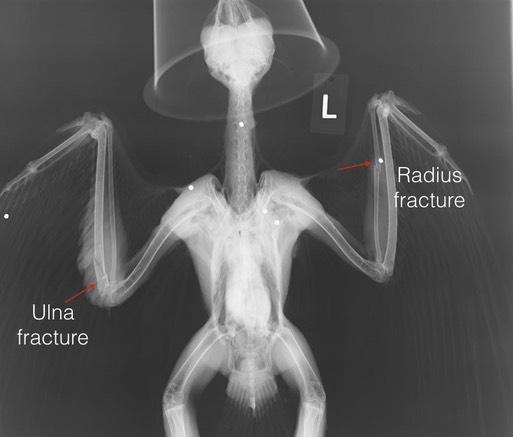

Lucky is probably not an appropriate name for this Red-tailed Hawk, although he is lucky that someone found him after he had been shot. Can you find the seven shotgun pellets in the radiograph below? Hint: one of the pellets is shattered. There are two wing fractures, the left radius and the right ulna. The radius fracture has a reasonable chance of healing without complications. The ulna fracture is near the elbow. There is damage in the elbow and the wrist looks suspicious.

There are an additional four pellets in his legs. The left halux is fractured. Hopefully it will still be functional after the fracture heals. In addition to two broken wings and a broken leg, the hawk has a blood lead level of 14.6 micrograms/deciliter. He has completed one course of chlelation. We will retest the lead this week .